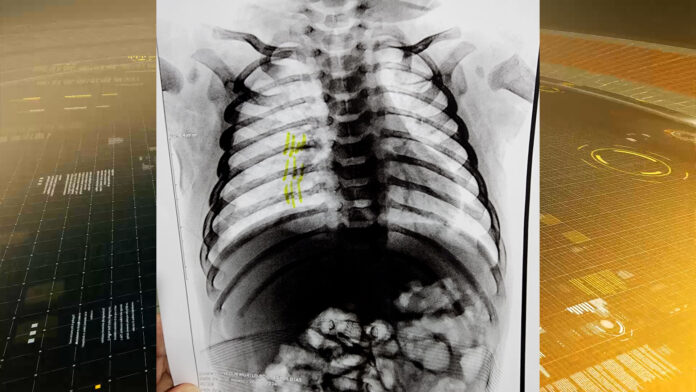

Em entrevista, o delegado Ruiter Martins destacou a gravidade das lesões:

“As lesões incluem fraturas no tórax, ferimentos no pescoço e na cabeça.